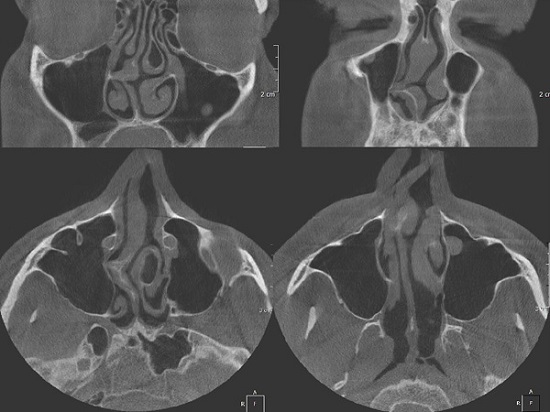

- Аномалии строения носоглотки и неблагоприятные внешние факторы: искривление или повреждение носовой перегородки; разрастание аденоидов (в данном случае ребенок дышит ртом почти постоянно или периодически в зависимости от стадии патологии); врожденная аномалия строения органа дыхания; слишком сухой воздух в комнате, где спит малыш (при этом нос обычно закладывает по утрам).

При аномалиях строения носа, имеющих врожденный или приобретенный характер, может быть рекомендовано оперативное вмешательство. Его также проводят и при разрастании полипов или аденоидов. Обычно врачи практикуют щадящие хирургические методы, например, эндоскопию. После проведения данной манипуляции восстановительный период достаточно короткий. В ряде случаев разрастание аденоидов можно остановить консервативными способами.